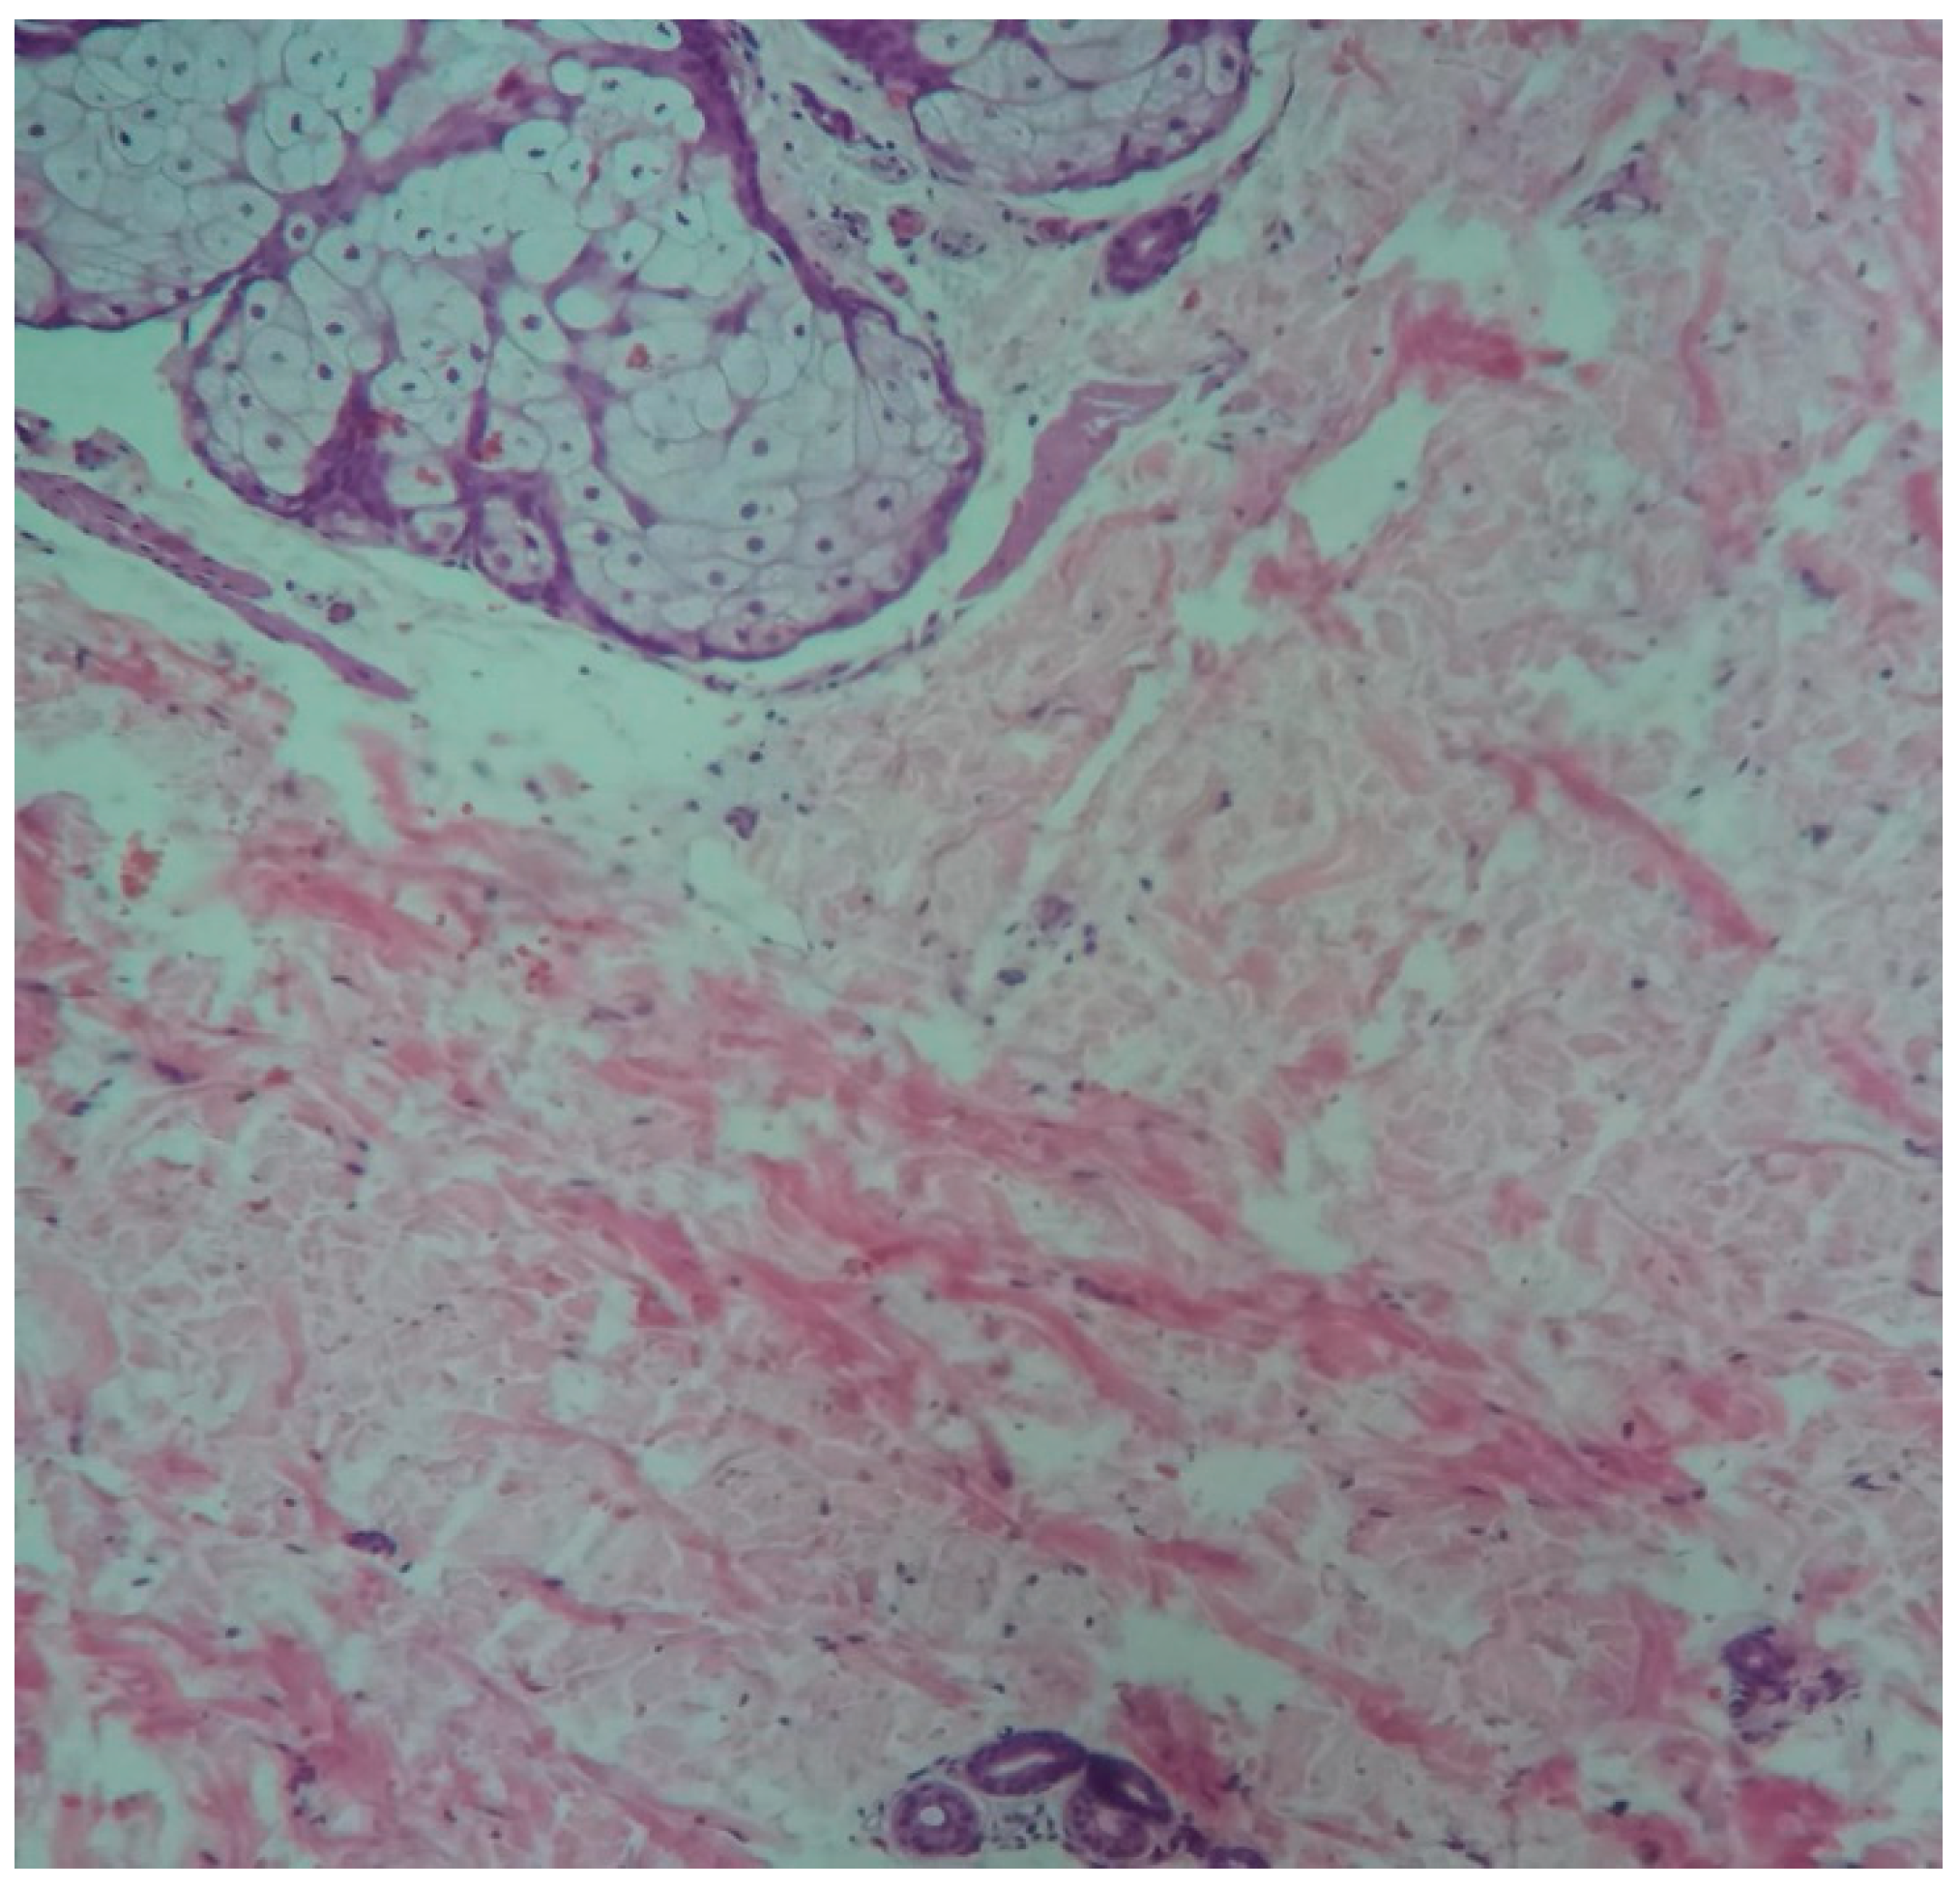

Histopathological analyse describe to the melanocytic nevi located on various regions of the body, with asymmetry, irregular form, cytologic atypia, and mitotic activity. Medical specialists, describe and conclude that to benign melanocytic nevi, could be possible to describe atypical pathological characteristics and more important good to mention characteristics when benign nevi are traumatized.(Figure 3) Dermoscopy play a role for a proper diagnostic important in practice to all ages, including, youth age and children.

Figure 3. Traumatic pigmentar nevus and adjacent region H&E stain x10.